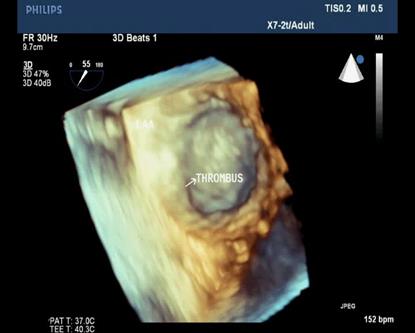

Because patients often presented late in Hospitals, their Wilkins score usually is high (68% with Wilkins score is superior to 8). Especially, LAA thrombus, even small size, furthermore, can be detected more clearly on RT- 3DTEE. Volume and mobility of LAA thrombus appreciated better on 3DTEE.

Detection LA and LAA thrombus by RT-3DTEE is more sensitive than 2DTEE with X-plane mode and 3 D Zoom only are avaible in 3DTEE.

Figure 5. 3D Zoom imaging demonstrating LAA with thrombus inside

Figure 7. LAA three dimensional view with thrombus attached to LAA wall

Figure 8. 3DTEE with icrop function shows thrombus attached to LA wall

Assessment of consequences on the LA and LAA ( study LA volume, LAA thrombi ) using X-plan function and 3D Zoom should be preferred because it is accurate and strongly related to predicting thromboembolic events and detecting thrombi [15]. Thrombi in LA and LAA were recorded on 24 patients with AF and 4 patient with sinus rhythm in our study results.